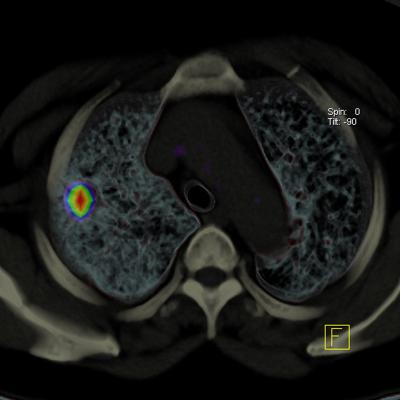

CompleWare software and contract research organization (CRO) services will facilitate complete respiratory development programs. This will provide specialized experts to support global respiratory trials. VIDA and CompleWare will provide precision lung imaging informatics, delivered through core lab imaging services (Precision Services) and interactive software (VIDA|vision). This solution spans the care cycle, from detection through treatment across a range of pulmonary diseases: COPD (including severe emphysema, chronic bronchitis), lung cancer and asthma.

The CompleClinical application from CompleWare is a comprehensive eClinical solution for clinical trial data capture and management. The VIDA|vision pulmonary suite of software and services provides full breadth and depth of analysis, empowering chest physicians with advanced, quantitative information to help inform care decisions.